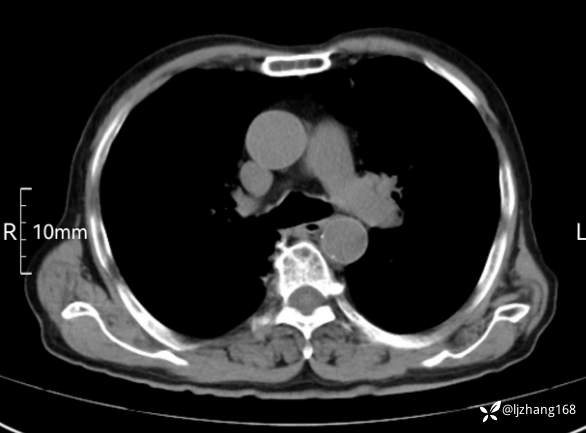

辅助检查:胸部CT:双肺肺气肿,间质性病变,血气分析:PH 7.413, PCO2 29.2mmHg, PO2,81.8mmHg,乳酸 3.3mmol/1,剩余碱-4.0mmol/1,HC03 18.8mmol/1。全血超敏C反应蛋白:超敏C反应蛋白 135.60 mg/L、 白细胞 14x19^9/L,中性粒细胞11.6x10^9/L。